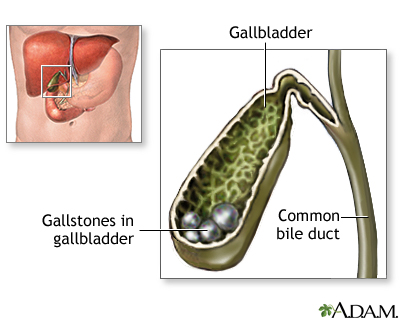

Formation of Gallstones (Cholelithiasis)

The process of gallstone formation is referred to as cholelithiasis. It is generally a slow process, and usually causes no pain or other symptoms. The majority of gallstones are either the cholesterol or mixed type. Gallstones can range in size from a few millimeters to several centimeters in diameter.

In adults, about 70% of gallstones are formed from cholesterol. Pigment stones (black or brown) are also very common and account for the remaining 30% of stones. Patients can have a mixture of the two gallstone types.

Choledocholithiasis (Common Bile Duct Stones)

Gallstones can also be present in the common bile duct, rather than the gallbladder. This condition is called choledocholithiasis.

- In most cases, common bile duct stones are secondary (they form in the gallbladder and pass into the common duct). About 10% of patients having surgery for gallstones have common bile duct stones at the same time.

- Less often, the stones form in the common duct itself. They are more likely to cause infection than secondary common duct stones.